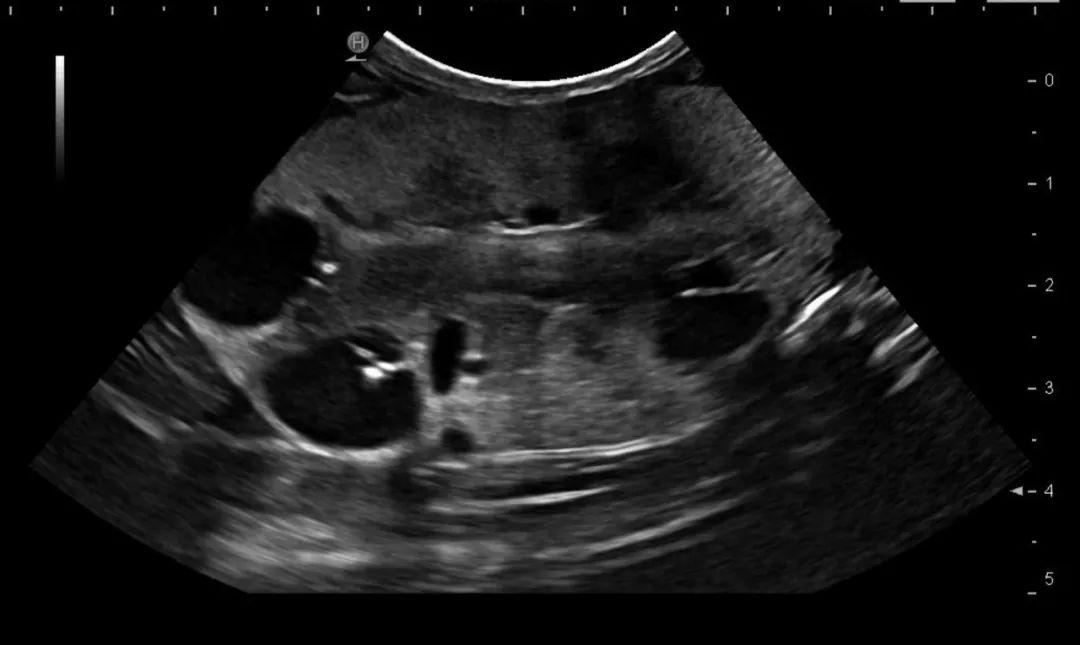

在 出生之时 ,肾脏中的水泡可能只有1mm或者更小,在大小超过2mm之前,一般是 难以察觉 的。B超检测多囊肾 要 等猫 9-10个月 之后,这时候的 准确度大致能达到91-98% 。[4] 只要有任何一个肾脏发现 至少一个无回声囊状暗区 ,结合高发品种,就可以大概率诊断为多囊肾病。

2岁异国短毛猫,超声发现双肾均有多个囊肿

(图片来源:中国农业大学动物医院影像中心)